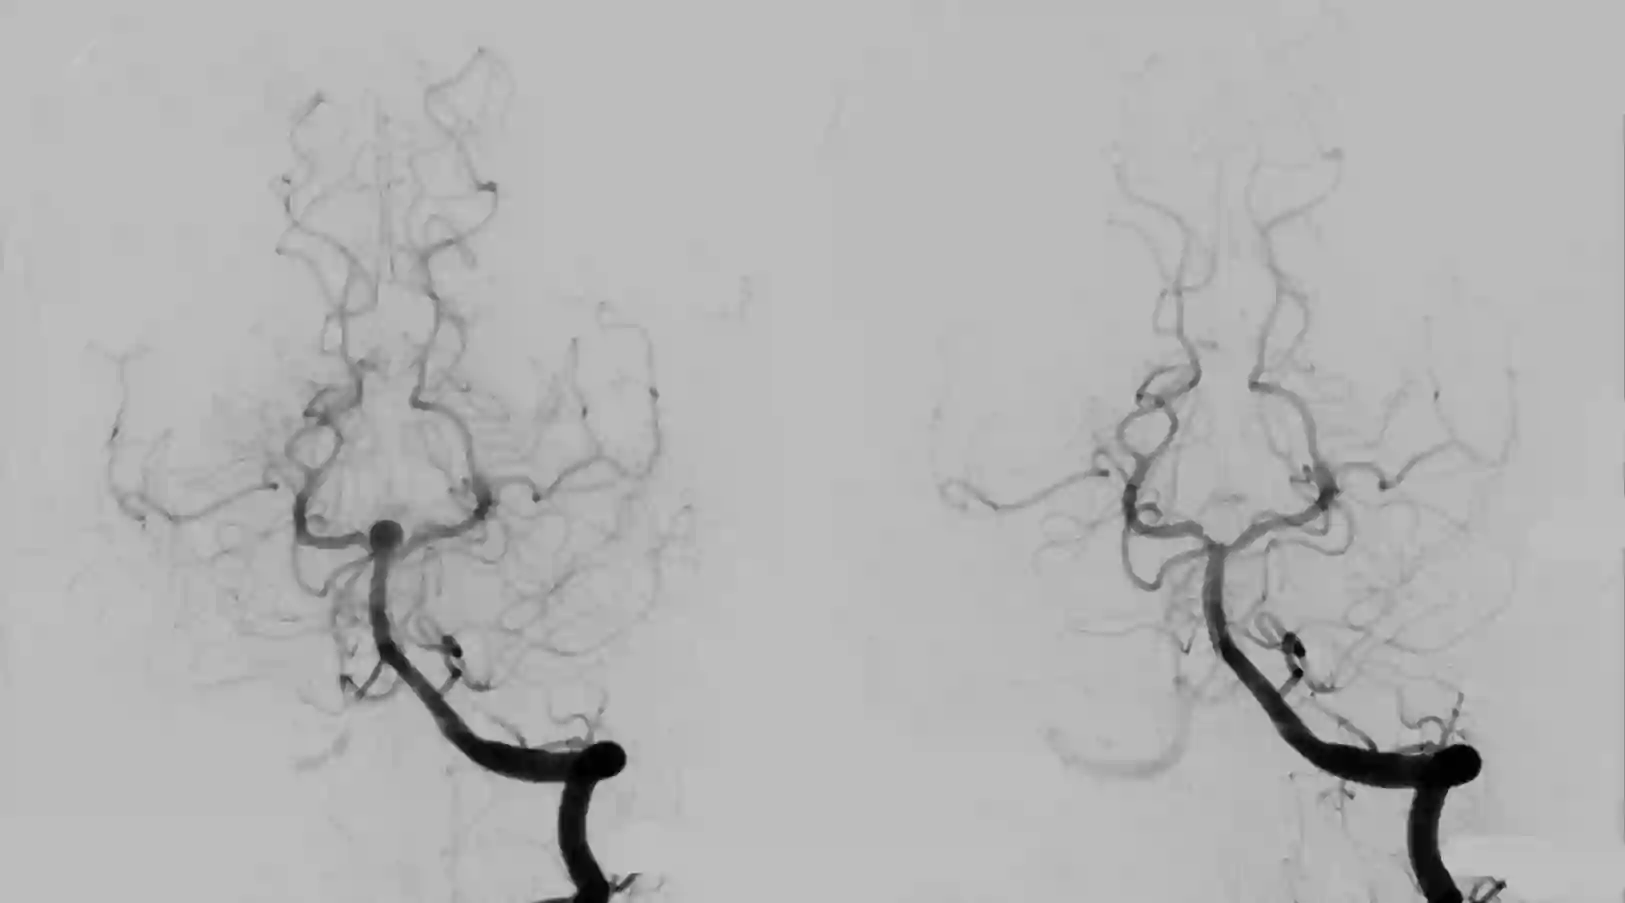

Der Goldstandard in der Diagnose von Basilarisspitzenaneurysmen ist die digitale Subtraktionsangiographie.

Videos

- Video Beschreibung

- Video einer endovaskulären Versorgung eines Basilarisspitzenaneurysmas mit einem WEB Device.